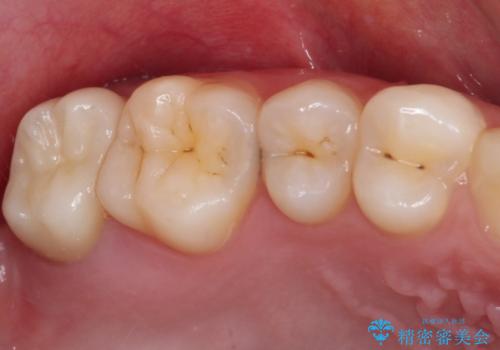

歯ぐきの形を整え、外れにくい被せ物を装着